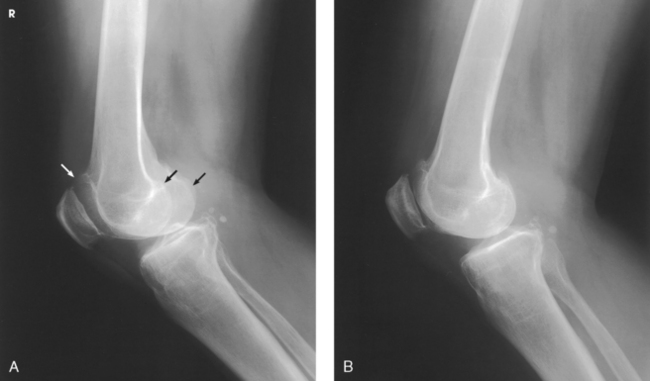

Structures shown: The resulting radiograph shows a lateral image of the distal end of the femur, patella, knee joint, proximal ends of the tibia and fibula, and adjacent soft tissue (Fig. 6-126).

Structures shown: The resulting image shows a lateral projection of the patella and patellofemoral joint space (Figs. 6-150 and 6-151).